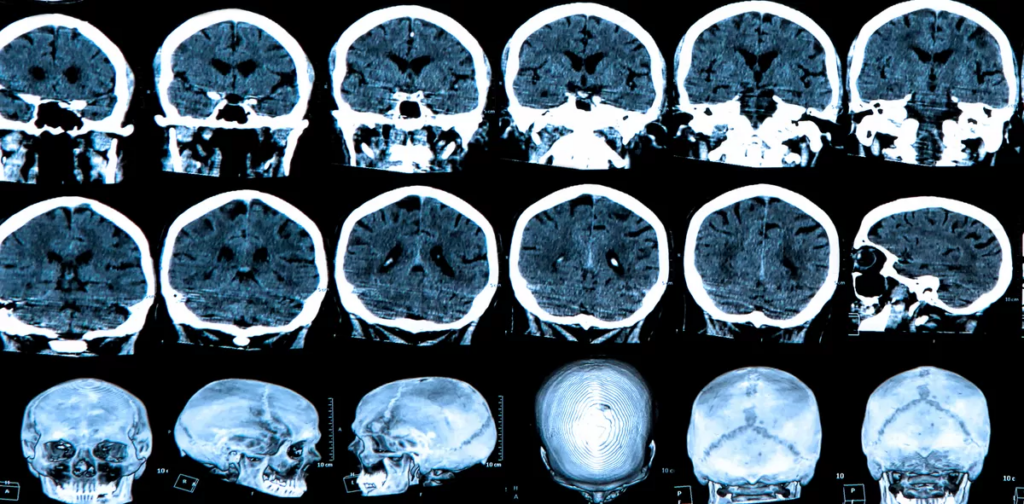

«El laboratorio de Beth Stevens, Ph.D., ha sido pionero en la comprensión de cómo la microglía, las células inmunes del cerebro, engulle y poda las sinapsis durante el desarrollo normal del cerebro. Ahora, han demostrado que este proceso de poda se reactiva anormalmente en enfermedades neurodegenerativas como la enfermedad de Huntington, la enfermedad de Alzheimer y la esquizofrenia.»